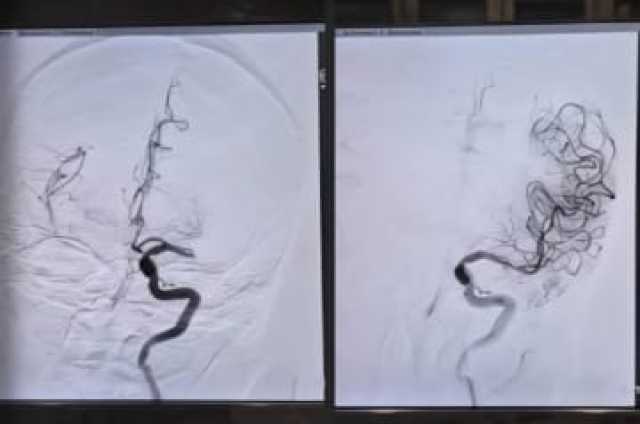

وبعد استقرار حالتها الأولية، تم نقل المريضة بشكل عاجل إلى مستشفى الأمير محمد بن عبدالعزيز، حيث خضعت لعملية إزالة الخثرة عبر القسطرة الدماغية، ضمن برنامج الأشعة العصبية التداخلية الذي أُطلق حديثاً، كجزء من مسار السكتات الدماغية.